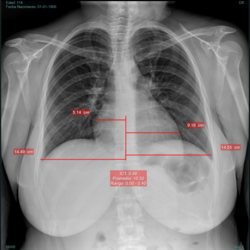

Índice cardiotorácico